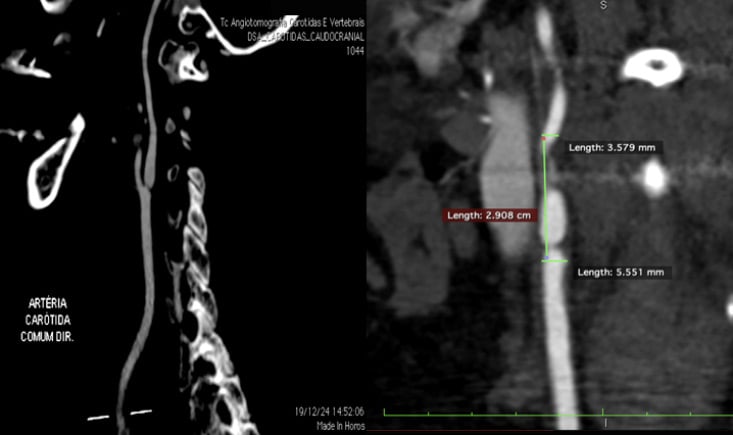

An asymptomatic 61-year-old woman, hypertensive, dyslipidemic, and obese, was diagnosed with a critical subocclusive stenosis at the ostium of the right internal carotid artery.

Imaging revealed a straight, non-tortuous vessel without atheromatous plaque, suggesting an actinic origin related to previous breast cancer radiotherapy. The patient had undergone bilateral mastectomy earlier in 2025 and was on antihypertensive, statin, and antiplatelet therapy.

- Angio CT: confirmed straight artery, no tortuosity, and without atheromatous plaques. Type I arch.

→ Hypothesis: actinic stenosis

NO atheromatous plaques